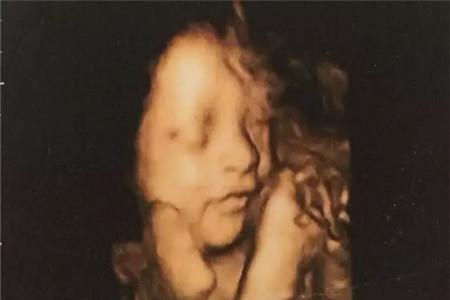

做了很多次产检后就变得轻车熟路了,不过在产检时还是有很多需要注意的点,一般来说孕妈在怀孕22-26周的时候就要在医生的帮助下进行畸形大排畸的四维检查,这时候可能就会出现一些孕妈没不了解的小知识,孕妈们需要注意下列这些问题。

在产检前孕妈们也不要太过于紧张,保持良好的心态来面对产检,如果孕妈过于紧张的话可能会影响到胎儿的活动。特别是在四维彩超检查中,如果宝妈过于紧张,宝宝在肚子里也会有所感知,很有可能就会“害羞”的不露脸了。另外孕妈也不用太过于计较宝宝的性别,特别是在做B超检查时,千万不要对着宝宝照太久了,虽然超声波对宝宝的身体是没有影响的,但是仪器产生的热效应对着宝宝时间久了,还是有些不利的,所以孕妈要注意。